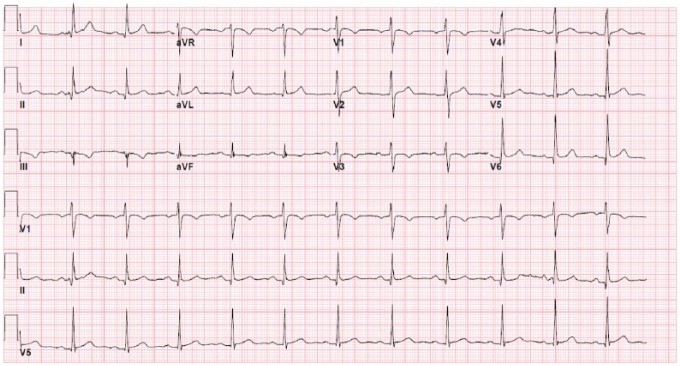

პაციენტს საწყის ეელექტროკარდიოგრამაზე აღენიშნებოდა სინუსური რითმი, Q – კბილები ქვედა განხრებში და არასპეციფიური ST სეგმენტის ცვლილებები ლატერალურ განხრებში.

გადაუდებელი დახმარების განყოფილებაში მისვლისას ფიზიკური გამოკვლევით არ გამოვლინდა ტემპერატურის მატება, პაციენტის ჰემოდინამიკური მდგომარეობა სტაბილური იყო. იგი თავს კომფორტულად გრძნობდა და არ აღენიშნებოდა რაიმე ტიპის მწვავე გამოხატულება. კარდიოვასკულარული გამოკვლევით გამოვლინდა გულისცემის ნორმალური სიხშირე და რეგულარული რიტმი შუილისა და ხახუნის გარეშე. ოტოსკოპიური გამოკვლევით პათოლოგიური ცვლილებები (გამონადენი, ტიმპანური შეშუპება ან სინათლის რეფლექსის დაკარგვა) არ აღინიშნებოდა. თავდაპირველმა ეკგ-მ აჩვენა სინუსური რიტმი Q-ტალღებით ქვედა განხრებში და არასპეციფიკური ST ცვლილებები ლატერალურ განხრებში . (სურათი1).

სურათი 1.

პაციენტი ჰოსპიტალში გადაიყვანეს დაკვირვებისთვის იმის გათვალისწინებით, რომ მას დატვირთული კორონარული არტერიების დაავადების დატვირთული ანამნეზი ჰქონდა. მისი საწყისი ტროპონინი ნორმალური იყო, მაგრამ შემდგომ 24 საათში მიაღწია პიკს 20.00 მგ/მლ. ტრანსთორაკალური ექოკარდიოგრამა ინტერპრეტირებული იქნა შემდეგნაირად: განდევნის ფრაქცია 60%-დან 65%-მდე, აშკარა სარქვლოვანი ან კედლის მოძრაობის ანომალიები არ ფიქსირდებოდა. ტროპონინის მატებასთან ერთად, განმეორებითმა ეკგ-ებმა აჩვენა სინუსური ბრადიკარდიის განვითარება წუთში 48 დარტყმით ST სეგმენტის მნიშვნელოვანი ცვლილებების გარეშე. გულის ბიომარკერების მნიშვნელოვანი მატების გამო მას ჩაუტარდა გულის მარცხენამხრივი კათეტერიზაცია, რამაც გამოავლინა მეორე და მეოთხე მარგინალური ტოტების მნიშვნელოვანი ოკლუზიური დაზიანება (სურათი 2).